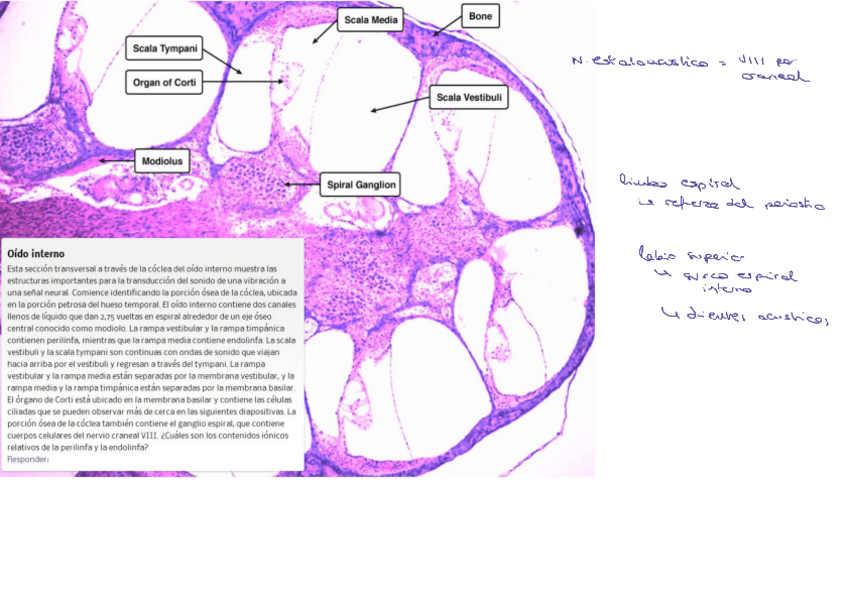

He publicado nuevos apuntes de 1º Histología Médica: T7.-oido.pdf

8 páginas

oido-ppt.pdf

He publicado nuevos apuntes de 1º Histología Médica: OIDO.pdf

6 páginas

Histologia-organos-de-la-audicion.pdf